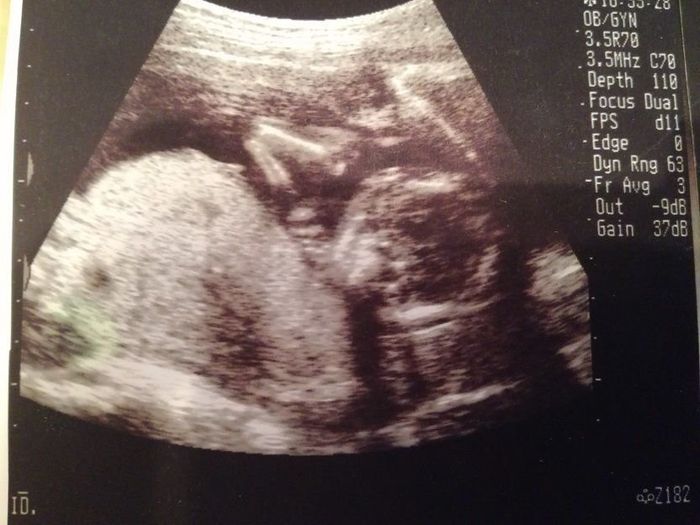

妊娠20週目のエコー写真

前回と今回の妊婦検診の間に、実は子宮の硬直と出血を起こして、自宅で安静している期間がありました。その間は、おなかの痛みと、絶え間なく頭に浮かぶ不安に耐える日々…。そのため、このエコー画像で元気な赤ちゃんの姿を確認した時は、体の奥が温かくなったのを記憶しています。顔に手を添える様子がほほ笑ましく、おなかを触りながら何度も見返しました。先生から「無理しない程度に、通常の生活に戻っていいよ」と言われました。